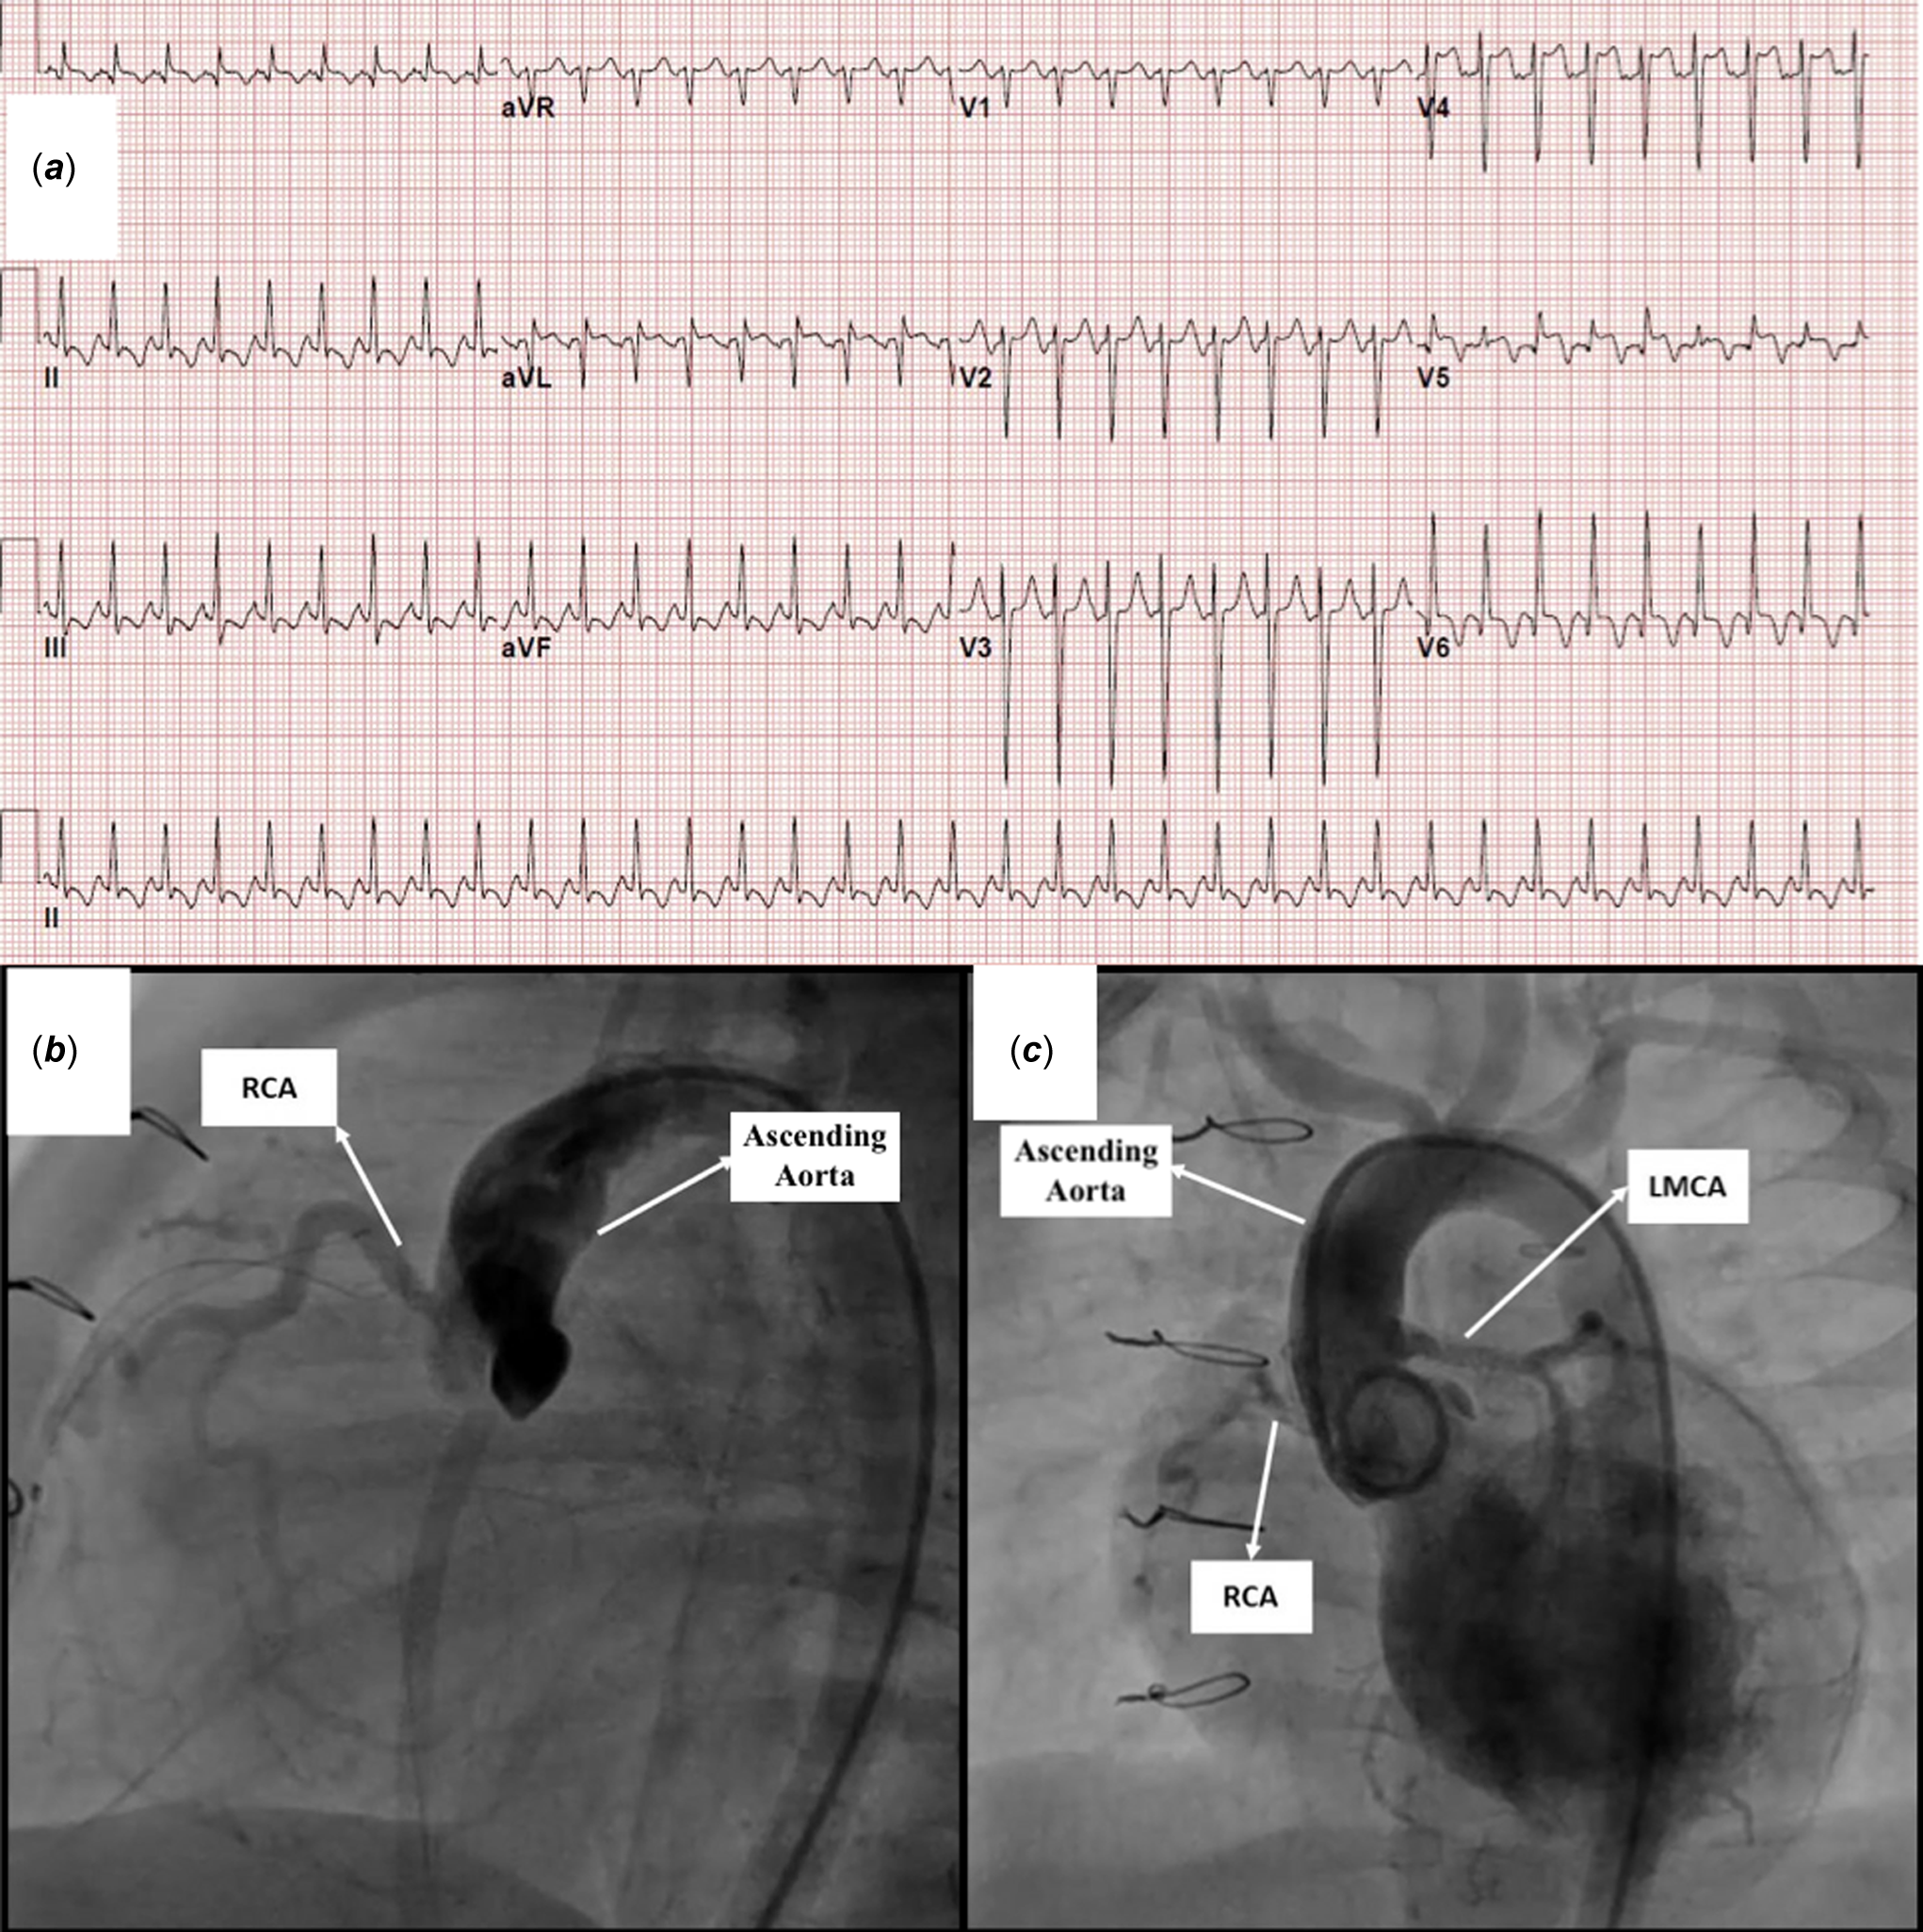

A two-month-old, 4.5 kg weight girl diagnosed with anomalous left coronary artery from the pulmonary artery and severe congestive heart failure was referred for surgery. Echocardiography revealed dilation of the left ventricle, reduced left ventricular ejection fraction ( 38%), a moderate degree of mitral regurgitation, and endocardial fibroelastosis (grade 2) (Figure 1). The electrocardiography showed pathological Q waves in the lateral lead (notable in aVL) (Figure 2a). Cardiac catheterisation demonstrated the anomalous origin of the left coronary artery.

Figure 2. a. Electrocardiography showing pathological deep Q waves in the lateral lead (notable in aVL). b: Aortic root angiogram demonstrated almost total occlusion of the left main coronary artery ostium at the anomalous left coronary artery from the pulmonary artery reimplantation site and retrograde filling from the right coronary artery. c: Post-intervention angiography showed reestablished flow to both the circumflex and the left anterior descending artery arteries.

The patient underwent left main coronary artery reimplantation in the ascending aorta above the sinotubular junction. Antegrade filling of the coronary arteries was observed in the echocardiography within the first 14 postoperative days. She was haemodynamically stable during this period. Whenever the patient was tried to be weaned from the mechanical ventilator, her haemodynamics deteriorated. At that time, echocardiography showed that the left main coronary artery was filled with the retrograde flow. Also, newly emerged ST-T changes were observed in the electrocardiography. In addition, serum troponin levels, which regressed to near normal on the 13th postoperative day, started to rise again on the 15th postoperative day.

On the postoperative 23rd day, diagnostic cardiac catheterisation was performed. Aortic root angiogram demonstrated almost total occlusion of the left main coronary artery ostium and retrograde filling from the right coronary artery (Figure 2b, Supplementary Video 1). The AR1 catheter (Cordis Europe, Johnson & Johnson Medical N.V., USA) was advanced retrogradely through the descending aorta with the help of 0.035 hydrophilic guidewire and placed into the coronary ostium. A 0.014” intermediate support straight tip guidewire was then used to cross the lesion and advanced into the left anterior descending artery (Supplementary Video 1). The 4 Fr femoral artery sheath was exchanged for a 4/5 Fr Glidesheath Slender introducer (Terumo Medical Corporation, NJ, USA), and 5F Cordis Vista Brite Tip JR 4 guiding catheter (Cordis Europe, Johnson&Johnson Medical N.V., USA) was advanced over the guidewire up to the left main coronary artery ostium. Percutaneous transluminal coronary angioplasty was performed using a The Mini Trek RX 1.5x12 mm non-compliant balloon. The procedure was repeated using a Simpass Plus 2 x 12 mm balloon(Supplementary Video 1). Coronary angiography revealed successful recanalisation despite ongoing mild stenosis in the proximal left main coronary artery (Supplementary Video 1). Stent implantation was decided to relieve stenosis constantly because of the high mortality and morbidity related to the repeated surgical procedure. Another 0.014” extra support coronary guidewire was placed into the distal the left anterior descending artery. The Alvimedica Commander 2.5x9 mm bare-metal stent was deployed in the left main coronary artery proximal to its bifurcation (Supplementary Video 1). Post-intervention angiography showed reestablished flow to the circumflex and the left anterior descending artery (Figure 2c, Supplementary Video 1). Heparin infusion (20 IU/kg/h) was administered for 24 hours. Thromboprophylaxis was initiated with aspirin (5 mg/kg/day) and clopidogrel (1 mg/ kg/day) on the next day.